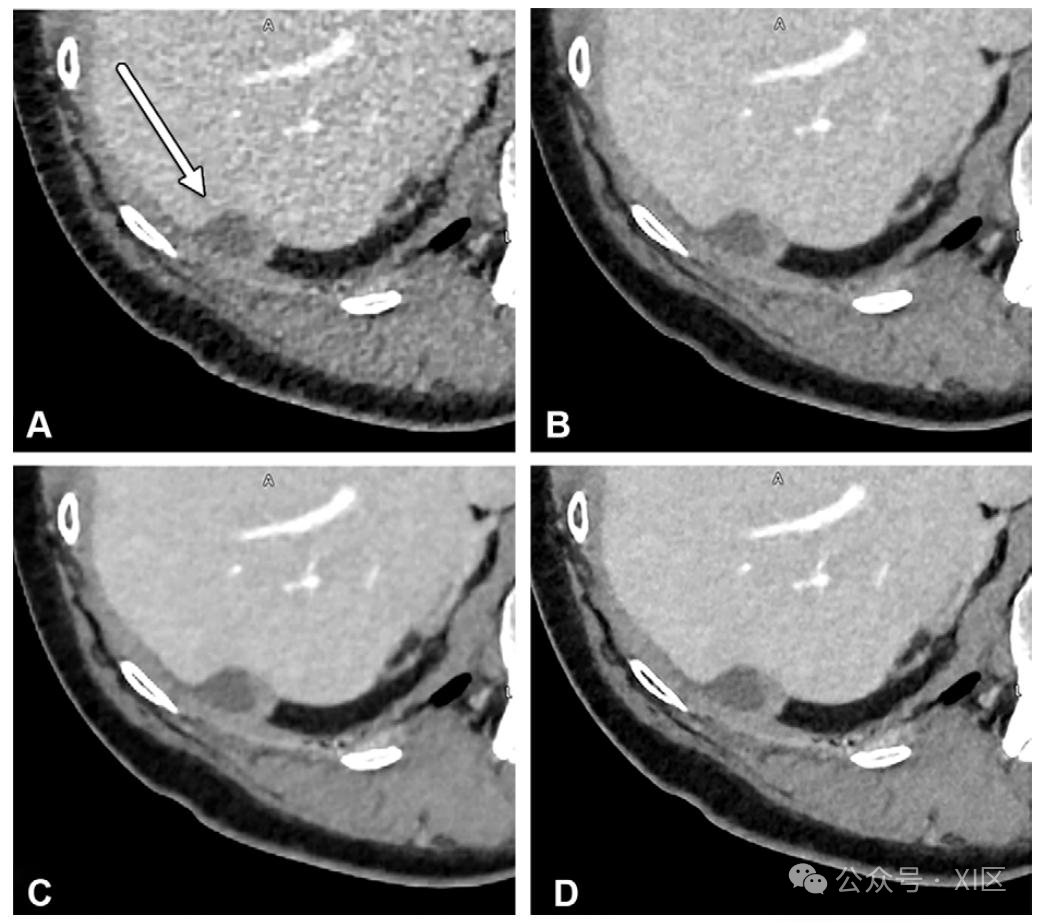

轴位增强 CT 图像显示肝被膜后方的微小转移瘤(A 图箭头所示)。初始采用三维自适应迭代剂量降低技术(AIDR 3D;佳能医疗系统)重建的图像噪声明显(A 图);经 AiCE 重建后,信噪比(SNR)和对比噪声比(CNR)显著改善(B 图);采用新型 PIQE 算法后,图像质量进一步提升,能更清晰地显示病变特征(如外壁增厚,C 图);必要时可将图像矩阵从 512 提升至 1024 以提高空间分辨率,结合 PIQE 算法可实现更优成像效果(D 图)。